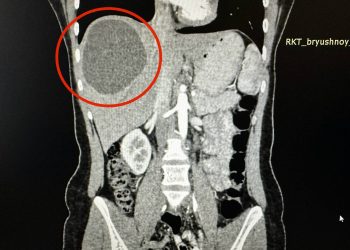

Врачи Республиканской клинической больницы помогли 41-летней жительнице Набережных Челнов удалить множественные миомы, сохранив матку. Об этом рассказали в пресс-службе клиники. ...